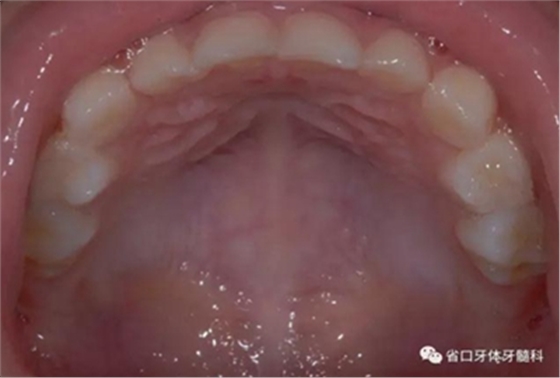

圖7 上頜牙相

乳牙期前牙反合分為牙性、功能性和骨性

牙性前牙反合:由于乳前牙牙軸傾斜度異常導(dǎo)致;

乳牙期前牙反合治療前先鑒別反合屬于牙性還是骨性反合,

頜墊舌簧適用于局部乳前牙反合的矯治或者替牙期局部前牙反合治療。